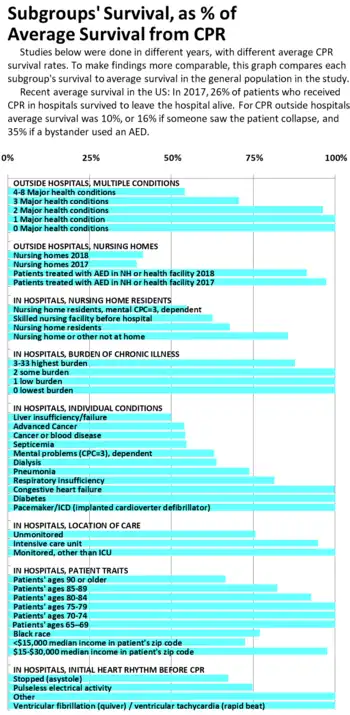

Survival differences, based on prior illness, age or location

The American Heart Association guidelines say that survival rates below 1% are "futility,"[122] but all groups have better survival than that. Even among very sick patients at least 10% survive: A study of CPR in a sample of US hospitals from 2001 to 2010,[73] where overall survival was 19%, found 10% survival among cancer patients, 12% among dialysis patients, 14% over age 80, 15% among blacks, 17% for patients who lived in nursing homes, 19% for patients with heart failure, and 25% for patients with heart monitoring outside the ICU. Another study, of advanced cancer patients, found the same 10% survival mentioned above.[123] A study of Swedish patients in 2007–2015 with ECG monitors found 40% survived at least 30 days after CPR at ages 70–79, 29% at ages 80–89, and 27% above age 90.[124]

An earlier study of Medicare patients in hospitals 1992–2005, where overall survival was 18%, found 13% survival in the poorest neighborhoods, 12% survival over age 90, 15% survival among ages 85–89, and 17% survival among ages 80–84.[125] Swedish patients 90 years or older had 15% survival to hospital discharge, 80–89 had 20%, and 70–79 had 28%.[124]

A study of King County WA patients who had CPR outside hospitals in 1999–2003, where 34% survived to hospital discharge overall, found that among patients with 4 or more major medical conditions, 18% survived; with 3 major conditions 24% survived, and 33% of those with 2 major medical conditions survived.[126]

Nursing home residents' survival has been studied by several authors,[73][125][97][127][128][129][130] and is measured annually by the Cardiac Arrest Registry to Enhance Survival (CARES). CARES reports CPR results from a catchment area of 115 million people, including 23 state-wide registries, and individual communities in 18 other states as of 2019.[131] CARES data show that in health care facilities and nursing homes where AEDs are available and used, survival rates are double the average survival found in nursing homes overall.[89]

Geographically, there is wide variation state-to-state in survival after CPR in US hospitals, from 40% in Wyoming to 20% in New York, so there is room for good practices to spread, raising the averages.[132] For CPR outside hospitals, survival varies even more across the US, from 3% in Omaha to 45% in Seattle in 2001. This study only counted heart rhythms which can respond to defibrillator shocks (tachycardia).[133] A major reason for the variation has been delay in some areas between the call to emergency services and the departure of medics, and then arrival and treatment. Delays were caused by lack of monitoring, and the mismatch between recruiting people as firefighters, though most emergency calls they are assigned to are medical, so staff resisted and delayed on the medical calls.[133] Building codes have cut the number of fires, but staff still think of themselves as firefighters.